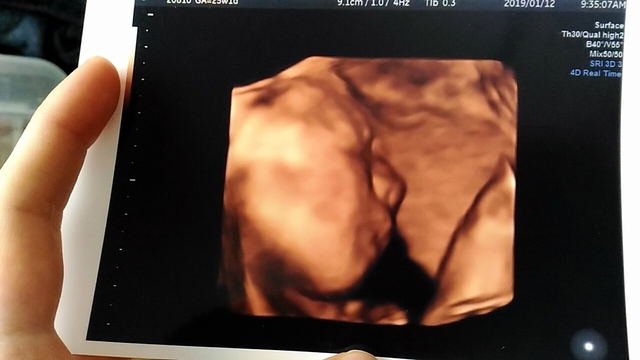

24週3日(24w3d・女の子)|keee_8 さん(23歳)

エコー写真撮影時のエピソード:

初めて顔がはっきりわかるエコー写真でした。こんなにもパパに似るものかと夫婦で笑い、お互いの家族に写真を撮る送りました。両親も自分たちの頃とは違ってよく顔がわかるね!と言っていました。

もちろん、パパに似てる!似すぎだ!!と大騒ぎです。旦那はうれしくて友だちにまで見せていました。